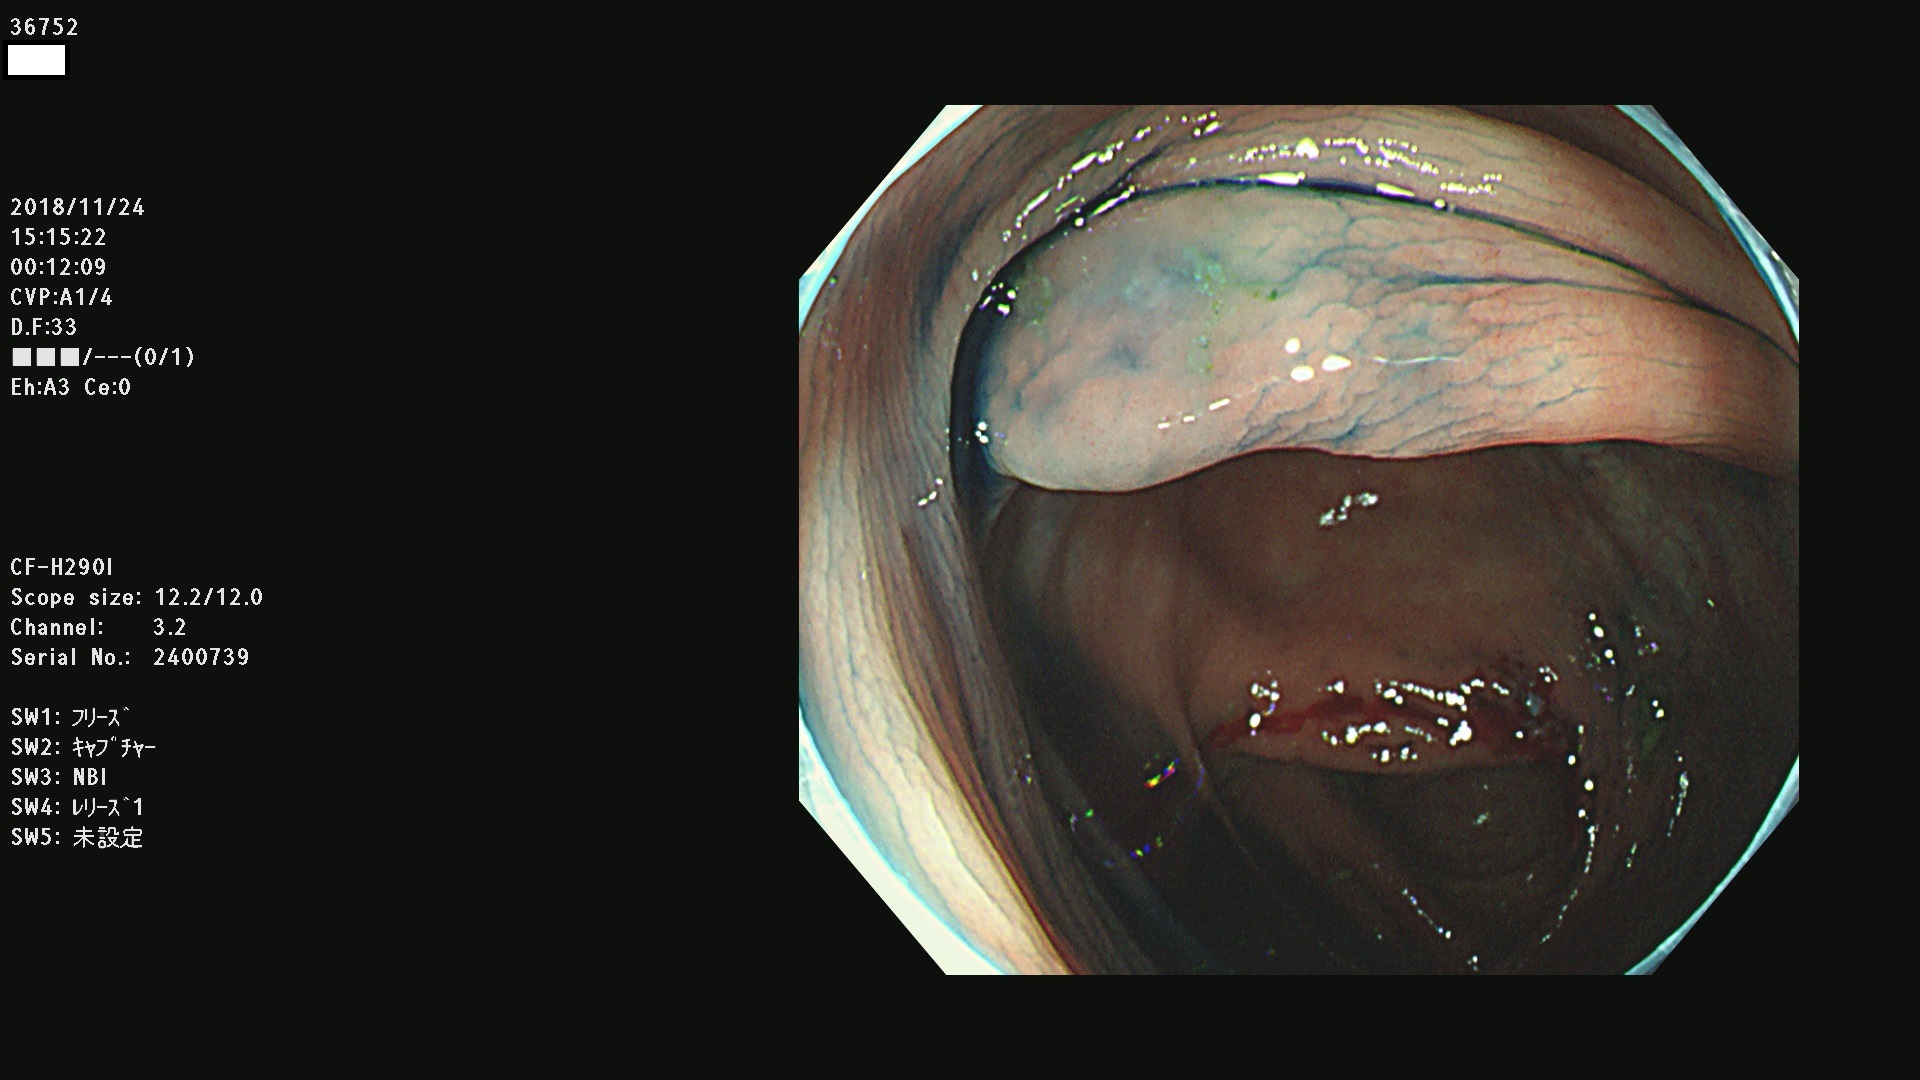

36700 36701 36702 36704 36705 36707 36708 36710 36712(SSAPのみ) 36714 36715 36716 36717 36718 36721 36723 36724 36730 36731 36732 36734 36735 36736 36738 36739 36742 36744 36745 36746 36749 36752(SSAPのみ) 36754 36756 36758 36759 36760 36731 36732 36734 36737 36738 36739 36771(SSAPのみ) 36772 36773 36774 36775 36776 36777 36780 36781 36783 36785 36786 36788 36790 36792 36794 36797 36798

発見困難で危険性の高い平坦型病変(上記100名より抽出)